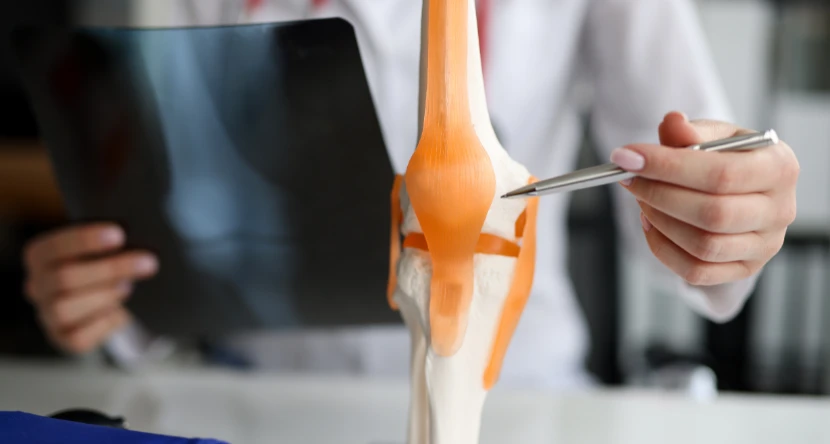

How Rheumatology Diagnosis Works at Amuka

Accurate diagnosis is the cornerstone of effective treatment. Our team at Amuka Orthopedic Clinic uses a combination of laboratory tests, imaging, and clinical evaluations to understand each patient’s condition.

- Imaging: High-resolution ultrasound and MRI to assess joint damage and inflammation.